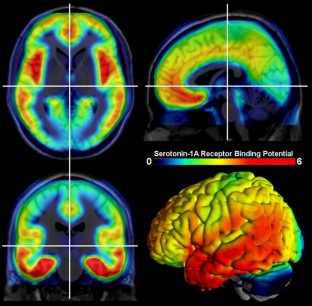

The serotonergic system is one of the most important modulatory neurotransmitter systems in the human brain. It plays a central role in major physiological processes and is implicated in a number of psychiatric disorders. Along with the dopaminergic system, it is also one of the phylogenetically oldest human neurotransmitter systems and one of the most diverse, with 14 different receptors identified up to this day, many of whose function remains to be understood. The system’s functioning is even more diverse than the number of its receptors, since each is implicated in a number of different processes. This review aims at illustrating the distribution and summarizing the main functions of the serotonin (5-hydroxytryptamin, 5-HT) receptors as well as the serotonin transporter (SERT, 5-HTT), the vesicular monoamine transporter 2, monoamine oxidase type A and 5-HT synthesis in the human brain. Recent advances in in vivo quantification of these different receptors and enzymes that are part of the serotonergic system using positron emission tomography are described.

Acknowledgments

We are grateful to Alexander Neumeister, Assoc. Prof., Mount Sinai School of Medicine and VA Connecticut Healthcare System, who provided 5-HT1B data for the figure. We thank the medical and technical teams of the Department of Psychiatry and Psychotherapy (S. Kasper, C. Spindelegger, P. Stein, M. Fink, U. Moser, E. Akimova, A. Hahn) and the PET Center at the Department of Nuclear Medicine (W. Wadsak, M. Mitterhauser, K. Kletter, R. Dudczak, G. Karanikas, L.-K. Mien, D. Häusler).